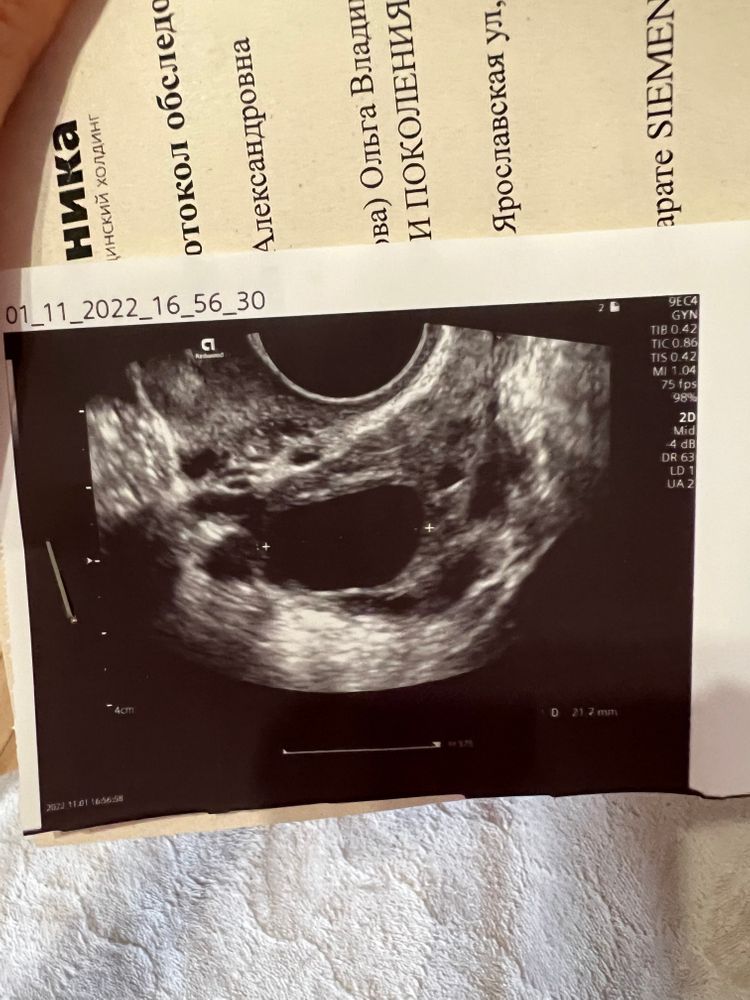

Nika , вот мой 22мм, который вчера похоже что лопнул уже).